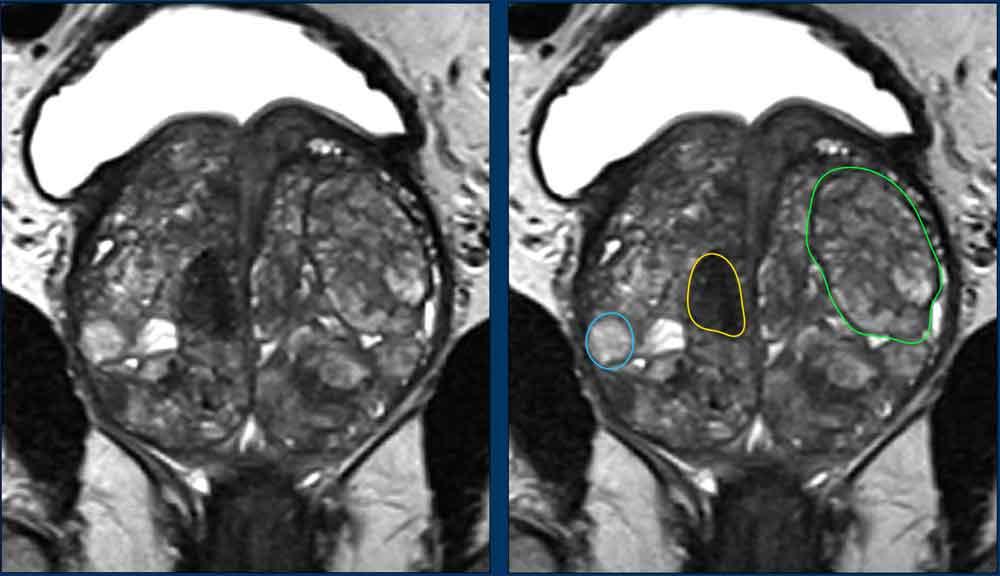

Hình ảnh

Ảnh chuỗi xung T2W mặt phẳng coronal này cho thấy nhiều loại nốt BPH khác nhau.

- Nốt tuyến (vòng tròn xanh dương)

- Nốt không điển hình (vòng tròn vàng)

- Nốt trong nốt (nhiều nốt nhỏ hơn nằm bên trong một nốt lớn hơn) (vòng tròn xanh lá).

Các nốt BPH chủ yếu là tuyến và teo nang biểu hiện tăng tín hiệu T2 mức độ vừa đến rõ, và được phân biệt với các khối u ác tính dựa vào tín hiệu và vỏ bao của chúng.